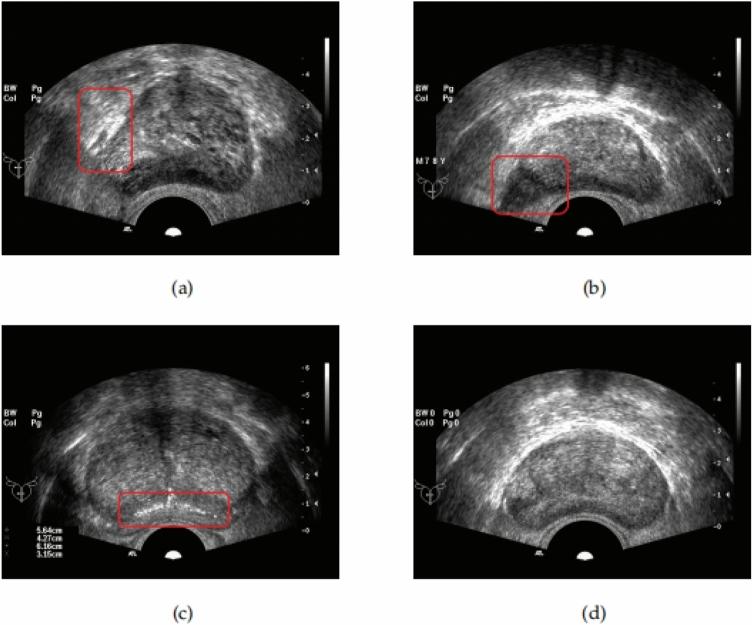

一种语义约束下的前列腺超声图像双向分割方法。

A bi-directional segmentation method for prostate ultrasound images under semantic constraints.

Due to the lack of sufficient labeled data for the prostate and the extensive and complex semantic information in ultrasound images, accurately and quickly segmenting the prostate in transrectal ultrasound (TRUS) images remains a challenging task. In this context, this paper proposes a solution for TRUS image segmentation using an end-to-end bidirectional semantic constraint method, namely the BiSeC model. The experimental results show that compared with classic or popular deep learning methods, this method has better segmentation performance, with the Dice Similarity Coefficient (DSC) of 96.74% and the Intersection over Union (IoU) of 93.71%. Our model achieves a good balance between actual boundaries and noise areas, reducing costs while ensuring the accuracy and speed of segmentation.

摘要

由于前列腺缺乏足够的标注数据,且超声图像中的语义信息广泛而复杂,在经直肠超声(TRUS)图像中准确、快速地分割前列腺仍然是一项具有挑战性的任务。在此背景下,本文提出了一种使用端到端双向语义约束方法的TRUS图像分割解决方案,即BiSeC模型。实验结果表明,与经典或流行的深度学习方法相比,该方法具有更好的分割性能,骰子相似系数(DSC)为96.74%,交并比(IoU)为93.71%。我们的模型在实际边界和噪声区域之间实现了良好的平衡,在确保分割准确性和速度的同时降低了成本。